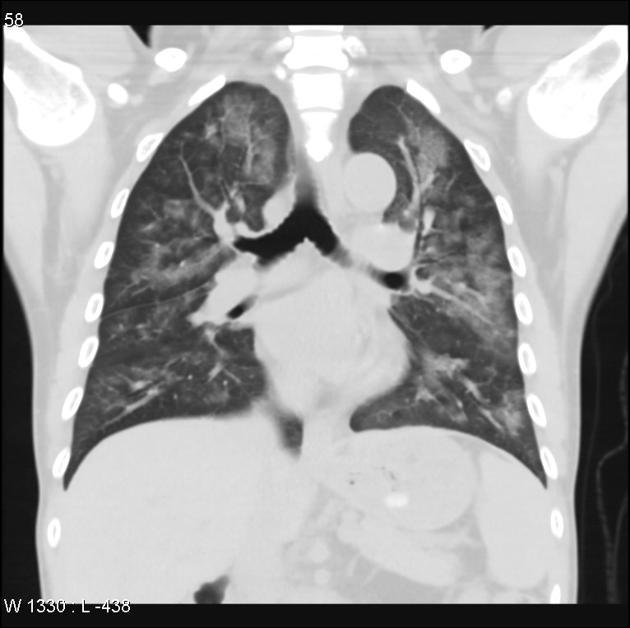

What is this pattern?

What is the etiology?

What disease processes can cause it?

Tree in bud pattern.

Caused by bronchiolar impaction and dilation by pus/mucus/fluid/inflammatory exudate.

Nonspecific- mostly caused by infections/inflammatory conditions. Possibilities include: active TB, MAI, viral pneumonia, fungal pneumonia, obliterative bronchiolitis, cystic fibrosis, immotile cilia syndrome, RA, and neoplastic.